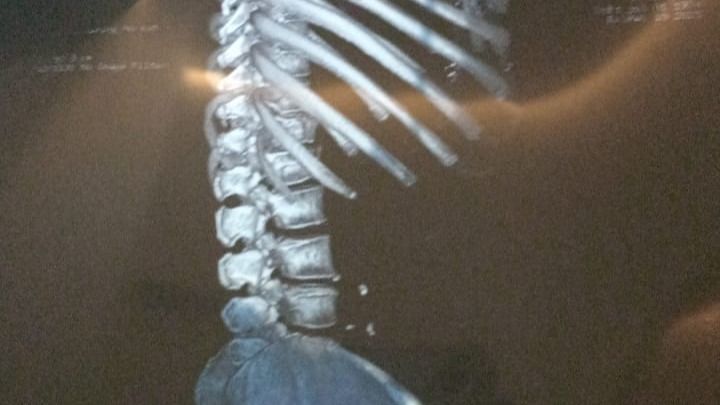

Se requiere una operación urgente para la señora Ma. Esther aguilar gomez que fue atropellada el pasado miércoles 19 de febrero del año 2025 la operación consiste en una cirugía de espalda de la lumbar 1 y lumbar 2 que llevará acabó el doctor Bulmaro Morales el día lunes 24 de febrero del presente año agradeciendoles de antemano a todas las personas de buen corazón por su apoyó y bendiciones gracias